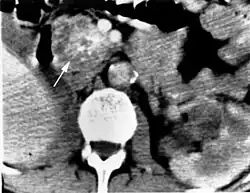

Das klinische Spektrum der Erkrankung umfasst neben den Affektionen von Augen und Kleinhirn das Auftreten von Hämangioblastomen im Bereich des Hirnstamms und des Rückenmarkes. Sodann werden Nierenzellkarzinome (Erkrankungsrisiko liegt bei 25 – 45 %, meist ab dem 50. Lebensjahr), Pankreaszysten, Phäochromozytome, Nebenhodenzysten und eine Polyzythämie beobachtet.

Die Diagnose VHL-Syndrom wird beim Vorhandensein von kapillären Hämangioblastomen (gefäßreichen Tumoren) im ZNS oder der Netzhaut des Auges gestellt. Weitere zum VHL-Komplex gehörende Tumoren (Phäochromozytom, Nierenzellkarzinom) oder eine entsprechende Familienanamnese treten hinzu. In der Kernspintomografie stellen sich die Hämangioblastome als kontrastmittelaufnehmende Knötchen dar.